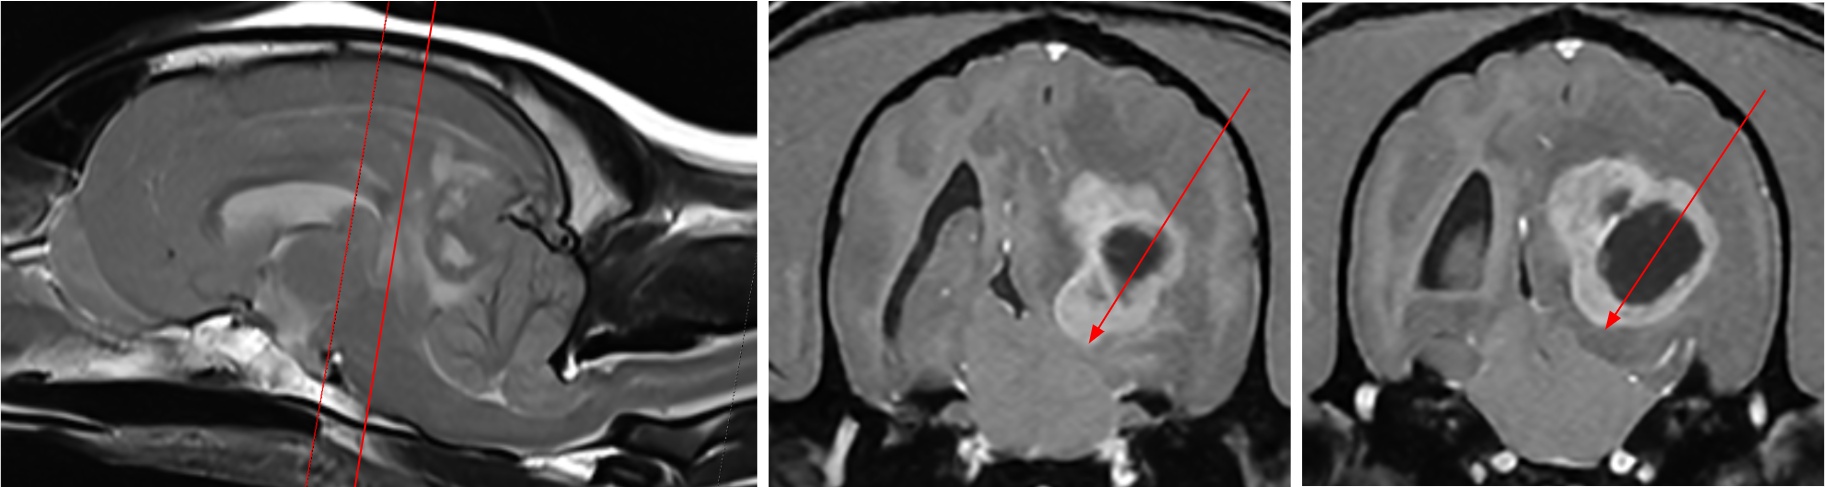

12살 암컷 웰시코기 환자는 기립불능과 의식 저하를 보이며 내원했다. 초기 신경학적 검사에서 전반적인 신경 반응 저하가 확인됐으며, 특히 연하반사 부재가 뚜렷해 중증의 뇌신경계 이상이 의심됐다. 뇌 MRI 촬영 결과, 좌측 대뇌반구 심부에 위치한 종괴성 병변이 확인됐으며, 영상학적 특성상 수막종(meningioma)의 가능성이 높게 판단됐다.

이외에도 광범위한 뇌부종, 대뇌낫의 우측 변위(midline shift), 소뇌 압박 및 탈출 소견이 함께 관찰됐다. 뇌간 압박까지 동반한 매우 위중한 상태였다.

환자의 종양은 뇌실질 내부(좌측 심부)에 위치한 형태로, 수의학에서는 기존에 확립된 접근법이 없었다. 이에 이안동물신경센터는 인의 신경외과에서 활용하는 Posterior Transcortical Approach를 적용했다.

이 술식은 측두–두정엽(temporoparietal region) 후방 피질을 통과하여 심부 구조로 접근하는 방법으로, 심부 종양 제거가 필요한 경우에 적합한 고난이도 술식이다.

의료진은 “이 접근법을 이용해 두개강 내로 안전하게 진입한 뒤 뇌간 인접 종양을 제거하여 뇌간 압박을 해소했다”며 “수술 중 제3뇌실의 정상적인 뇌척수액(CSF) 흐름도 회복됨을 확인했다”고 밝혔다.

수술 직후 촬영한 MRI에서 뇌간 압박의 완전한 소실이 확인됐으며, MRI 촬영 중 자발호흡도 회복됐다. 약 6시간 후 환자의 상태가 안정되어 발관도 가능해졌다.